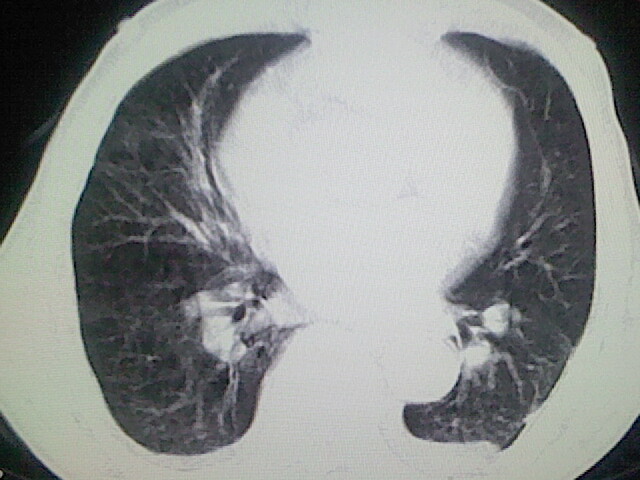

以下是引用zsl6918在2008-8-28 16:49:00的发言:[br]双肺炎性病灶,食管狭窄估计与心房增大压迫所致。

以下是引用xulianj在2008-8-28 20:36:00的发言:[br]慢支肺气肿伴感染,右上肺陈旧性结核;食道建议胃镜检查。

以下是引用wqs571018在2008-8-28 21:18:00的发言:[br]慢支继发感染,右上肺陈旧性结核;食道建议胃镜检查。